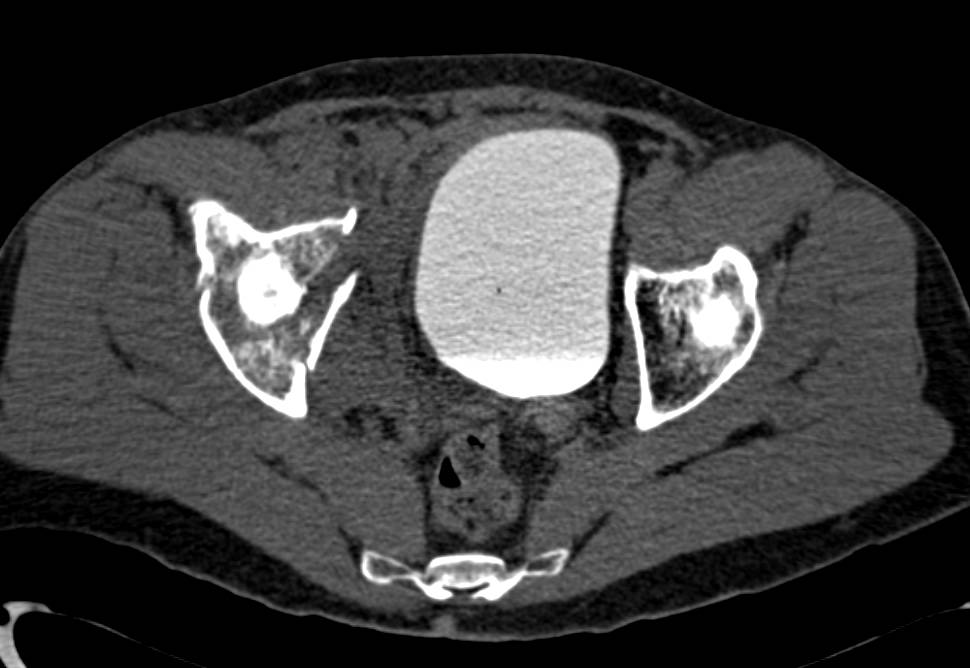

Trauma with CTA and CT Cystogram with Pelvic Fractures. No evidence of Vascular Injury